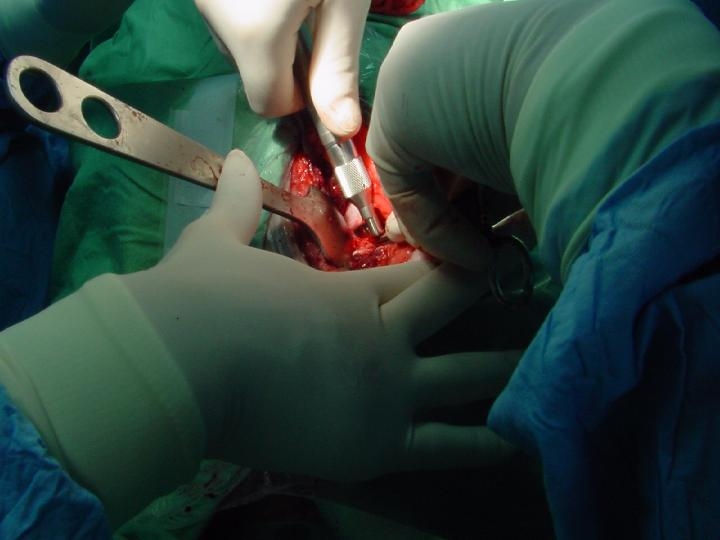

- Osteotomia do Ilium

Abordagem lateral do ilium. Os músculos glúteos são reclinados. Colocam-se os retractores de Hohman no bordo dorsal do corpo do ilium com a dupla finalidade de separar os músculos glúteos e obter uma melhor visão da zona.

Utiliza-se uma placa auxiliar DCP 5 orifÃcios que é moldada sobre o ilium. Colocada no eixo maior do ilium para determinar o eixo de rotação escolhido. São feitos 2 orifÃcios do lado acetabular em posição neutra e o orifÃcio junto à linha de osteotomia ao nÃvel da extremidade iliaca craneal é efectuado em posição excêntrica. A seguir fez-se a osteotomia do ilium entre o orifÃcio acetabular e o orifÃcio iliaco préforado com uma inclinação de 10º para a frente em relação à perpendicular ao eixo do ilium. Seguidamente coloca-se uma pinça de redução na tuberosidade do isquim através da abordagem anterior para ajudar a rotação do acetábulo. Neste membro o fragmento distal do ilium encavalita sobre o fragmento proximal. Faz-se a osteotomia deste fragmento distal. A placa AO/ASIF ∢ 45º é fixada na posição definitiva; os parafusos do fragmento acetabular são colocados numa 1ª fase depois os parafusos do fragmento iliaco préforado é posicionado. Finalmente os dois orifÃcios proximais do ilium são forados e colocado os parafusos.

Finalmente faz-se a tensão do arame de cerclagem de ischium.